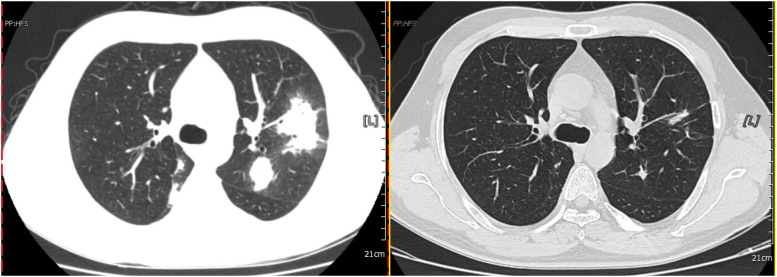

Results: Most patients in the PC group are male (59.6%), with an average age of 49.4 years. Most of the patients have no underlying disease (51.9%). Diabetes and hypertension are the most common comorbidities. Most patients (53.8%) are asymptomatic. Cough and sputum are the most frequent clinical symptoms, followed by fever and chest distress. Nodules and exudative consolidation are the most common imaging findings, and the culture positivity rate is 25%. Forty patients are positive according to the BALF GXM test, for a positivity rate of 83.3% and a negative predictive value of 91.8%. Moreover, 39 patients are positive according to the serum GXM test, for a positivity rate of 81.3% and a negative predictive value of 90.9%. The positivity rate for serum plus BALF is 95.8%. There is no significant difference (P > 0.05) in diagnostic value between BALF and serum GXM tests for PC. GXM positivity rates differ significantly among paired BALF, serum, and BALF plus serum groups (P < 0.05).

Abstract Image